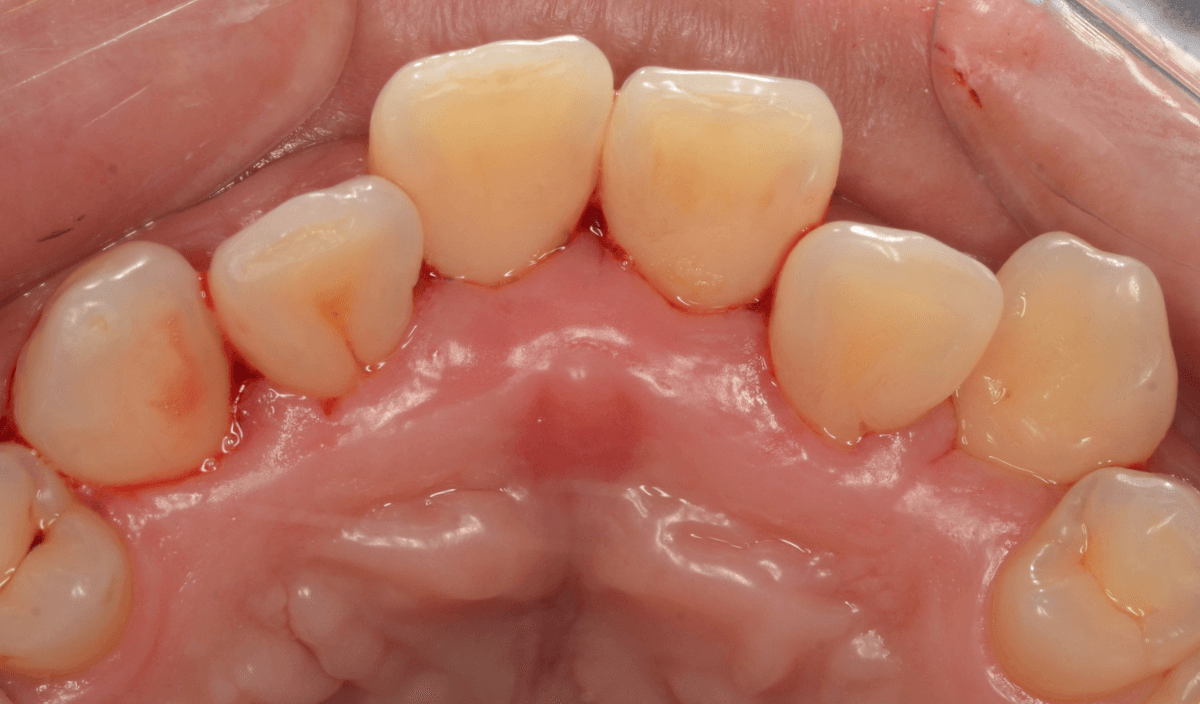

Case.3 縁下歯石除去後、3か月の状況

今回は、下の前歯の縁下歯石を除去した後、3か月後のメンテナンスにいらっしゃった方の治療前後です。

前側から見た所です。

とても綺麗に歯肉が治っているのがわかると思います。

歯石除去が終わったあとも、頑張ってお手入れしているのがうかがえます。

歯石除去だけでは、ここまで綺麗には治りません。

裏側の歯肉の状態も大きく変わりました。

年齢もお若い方なので、歯肉の回復も早いです。

ある程度まで歯周病が進行してしまいますと、完全に歯肉が元に戻るのは難しくなってしまいます。

本格的な歯周病になる前に治療を受けていただけて、本当に良かったと思います。

あとは、油断せずに持続していただきたいと思っています。